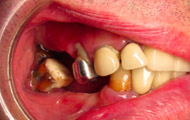

Exemple d’un implant unitaire pour remplacer une dent antérieure manquante.